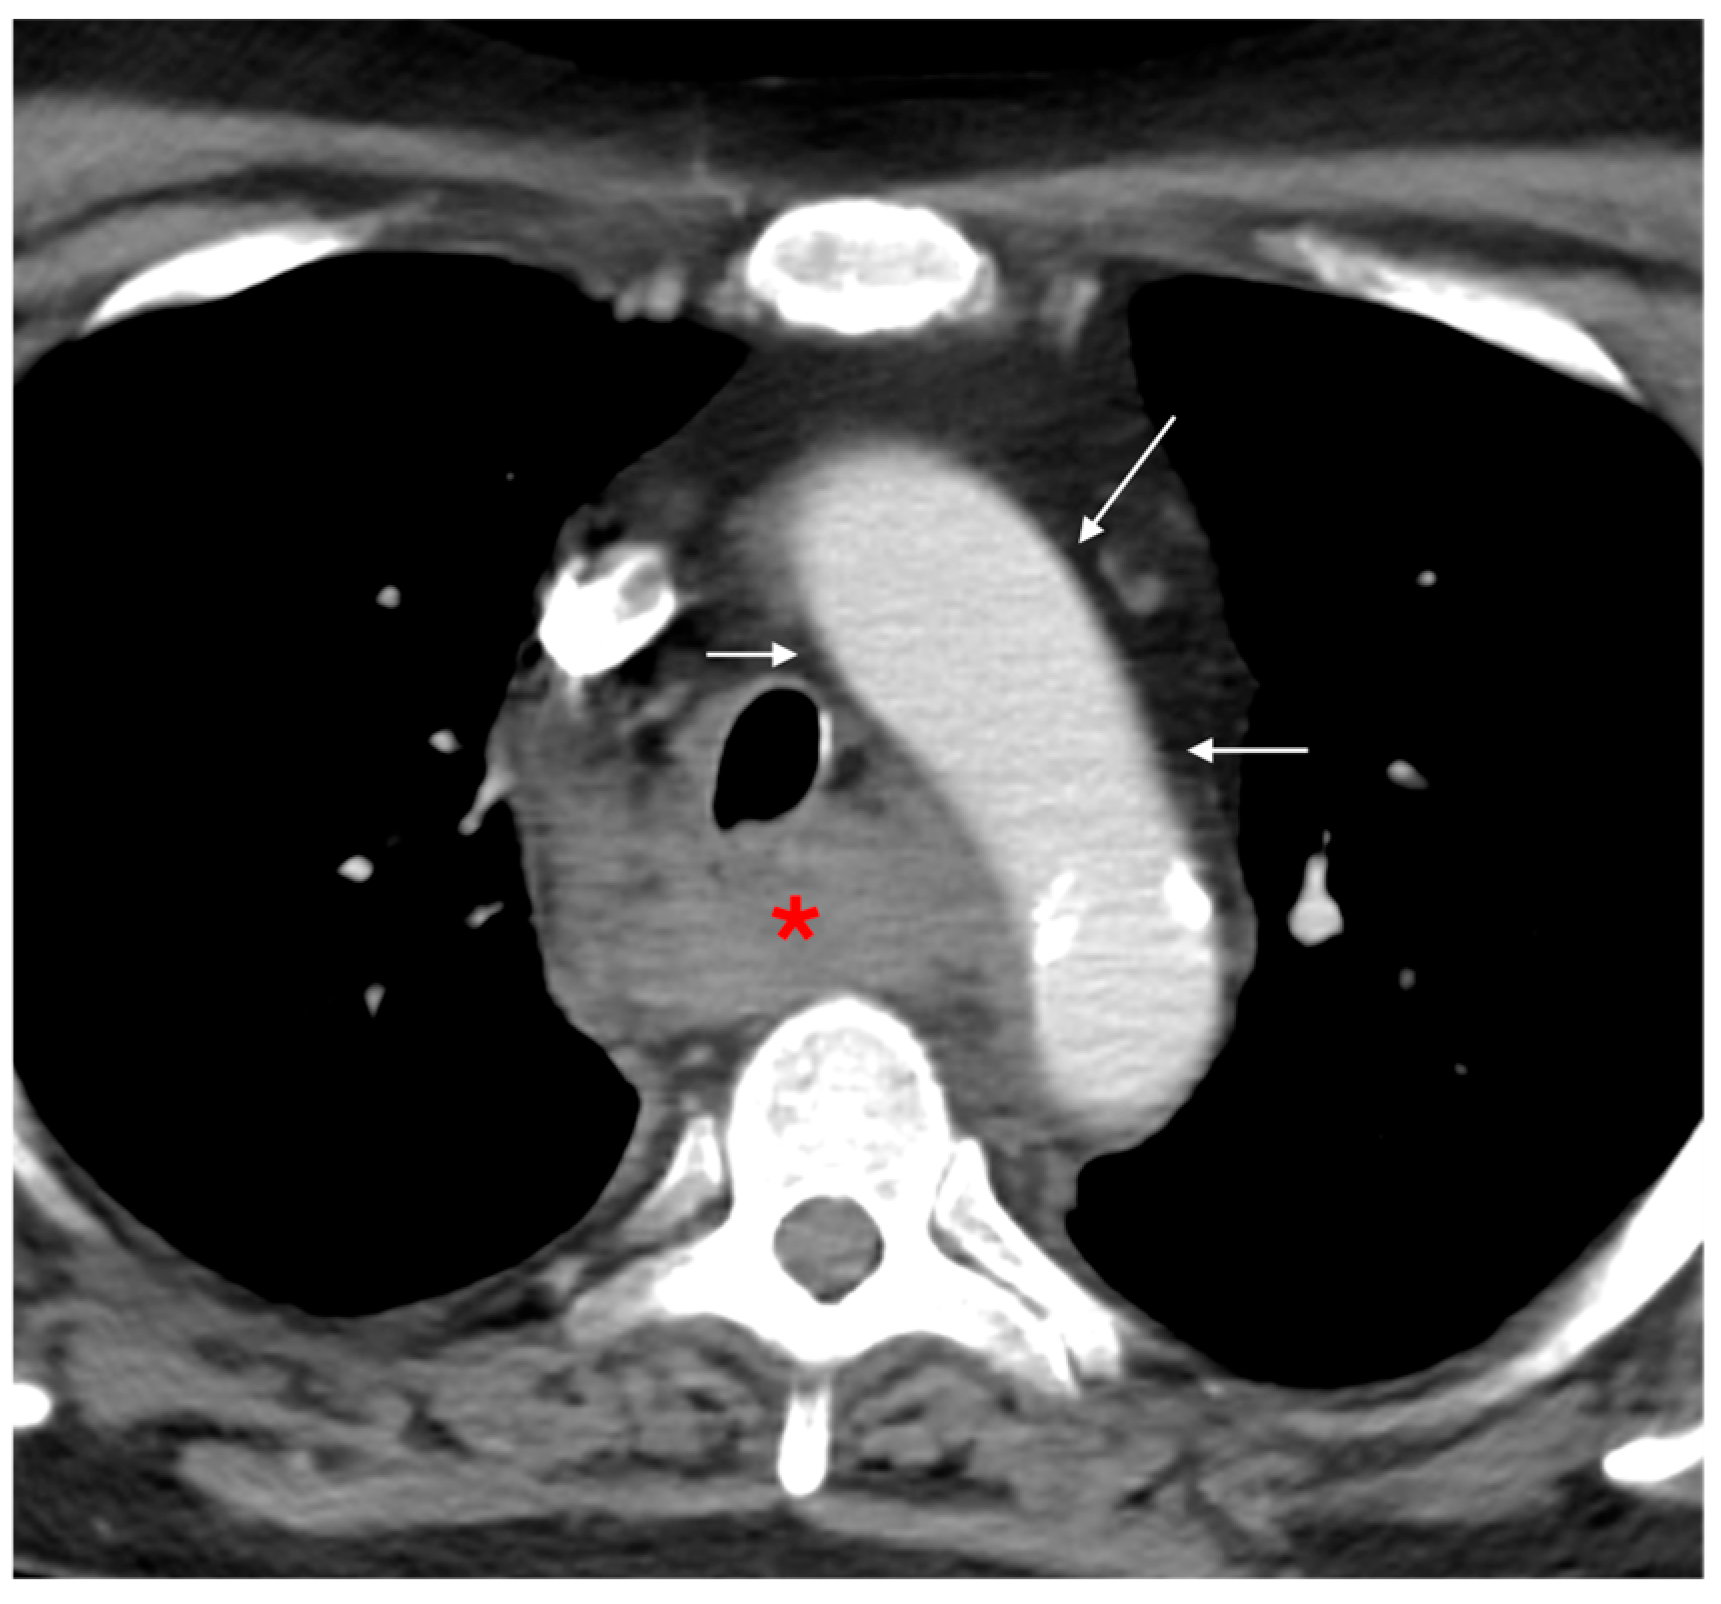

3.1.1. Direct Signs of Aortic Injury

3.1.2. Indirect Signs of Aortic Injury